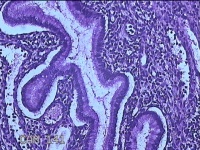

宫颈赘生物

性别

女

年龄

42岁

临床诊断

宫颈赘生物待查?

一般病史

阴道不规则流血15天。

标本名称

大体所见

灰白暗红色肿物1.3x0.7x0.3cm一个,表面糜烂。